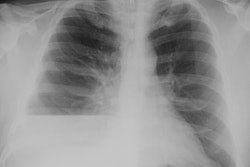

X-ray:

The lesion typically presents with a pleural effusion with associated smooth, nodular pleural thickening (resembling a mesothelioma).